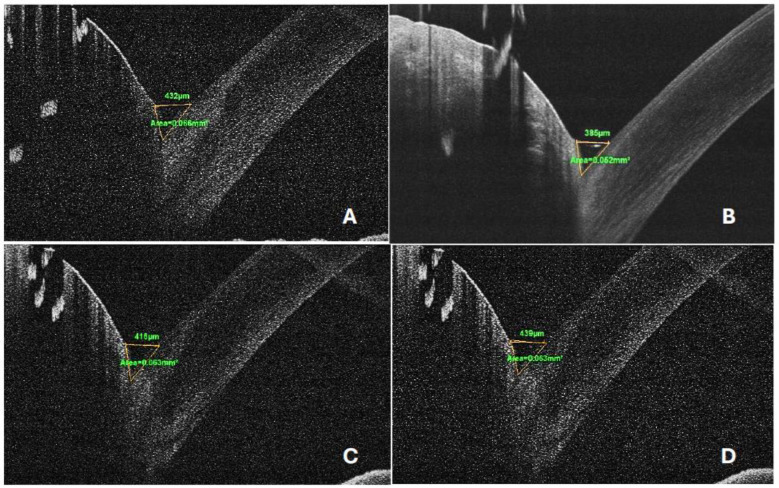

Methods: This non-randomized, prospective, interventional study consecutively recruited the right eyes of patients with dermatochalasis who underwent bilateral upper eyelid blepharoplasty at a tertiary center. Preoperative assessments included a standardized ophthalmic examination, ocular surface disease index (OSDI) questionnaire, Schirmer's test I, tear break-up time (TBUT) test, and anterior segment optical coherence tomography (AS-OCT) to measure tear meniscus height (TMH) and tear meniscus area (TMA). Postoperative evaluations were conducted at 1, 3, and 6 months. At the final follow-up, scar quality and patient satisfaction were assessed using the Patient and Observer Scar Assessment Scale.

Results: Fifty eyes of 50 patients with a mean (standard deviation) age of 47.1 (1.6) years were included. Statistically significant postoperative changes were observed in the OSDI score, Schirmer's test value, TBUT, and TMH at the 6-month follow-up (all P < 0.001). These parameters initially worsened at 1 month and then improved significantly at 3 and 6 months, returning to or surpassing baseline levels. TMA showed a transient postoperative decline, with full recovery at 6 months. Exceptionally strong positive correlations were found between TMH or TMA and TBUT or the Schirmer's test value at most follow-up visits (all P > 0.05). Patient satisfaction was high, with 95% reporting satisfaction with cosmetic outcomes, and no cases of visible or hypertrophic scarring were observed at final follow-up.